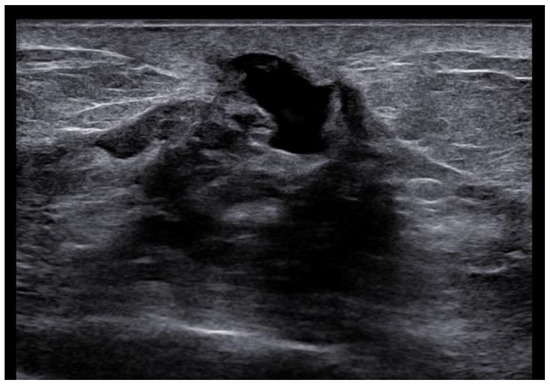

US is a non-invasive, repeatable, and widely available technique. Its inclusion in the initial assessment could benefit and warrants consideration, mainly when DM yields negative results, especially in women with denser breast tissue. Similar to mammographic MPD findings, US alterations are nonspecific and include expected changes for BC treatments, including hypoechogenic masses, microcalcifications, ductal ectasia, NAC flattening, asymmetry, and thickening [26,47,48] (Figure 5). Additionally, US offers an option of immediate image-guided intervention and improves the diagnostic accuracy for axillary lymph node status. However, not all underlying BC can be identified through the US. MRI’s higher sensitivity in evaluating the retroareolar region provides crucial information for clinically evident MPD cases with occult findings in DM and US and for the preoperative assessment of disease extent in patients eligible for breast-conserving therapy [26,47]. In addition, thanks to contrast enhancement, it shows nipple involvement [49]. MRI findings include asymmetric and abnormal NAC enhancement patterns, sometimes associated with non-mass-like enhancement or suspicious masses elsewhere in the breast [26,47,50], even a distant site with no apparent anatomic connection, about possible MPD multifocality and multicentricity (Figure 6). MRI may also evaluate lymph node status, raising concerns about axillary or internal mammary involvement. However, it is essential to note that false-negative MRI results for NAC evaluation in MPD cases have also been reported [25,50], probably for less-aggressive disease forms. Therefore, all clinically suspicious findings must undergo biopsy, regardless of negative imaging results. A full-thickness NAC biopsy with histological and immunohistochemical evaluation is the gold standard for establishing an ultimate diagnosis [38]. Research examining the molecular markers in MPD cases has revealed an expression of HER-2/neu, cytokeratin 7 (CK7), mucin 1 (MUC1), and human milk fat globule, and positive staining with CAM 5.2 antibody [51,52]. Exfoliative cytology with PC demonstration may be helpful, but a negative result can occur; its use has been postulated as an easy screening test for eczematous skin changes to the nipple.

Figure 5.

Woman with pruritic erythema and serous discharge of the right nipple and history of ipsilateral nipple-sparing mastectomy (10 years prior). Exfoliative cytology was performed with PC positivity. In the US, superficial hypoechogenic retroareolar areas with ectasia ductal are observed.